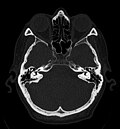

-

Craniale Computertomographie Abgebildet sind Felsenbein und Nasennebenhöhlen. Aufgrund der hohen Auflösung der Aufnahme des verwendeten 64-Zeilen-CTs sind selbst die Gehörknöchelchen erkennbar. -